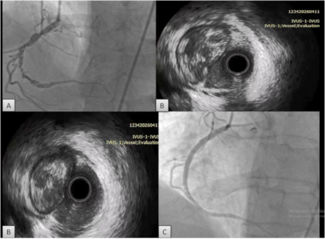

A transthoracic echo followed by transesophageal echo obtained after the coronary procedure in the coronary care unit showed a 2.5 cm visible movable thrombus over the atrial surface of the mechanical mitral valve (Figure 4), and almost normal systolic left ventricular function with mild apical hypokinesia. Levels of troponin T and CK were actually raised up to 4.8 ng/mL and 900 IU/L, respectively. The patient was commenced on heparin continuous IV infusion, and a cardiothoracic reintervention was performed 1 week later, confirming the existence of a voluminous thrombus over the prosthetic mitral valve and proceeding in a replacement of the thrombosed valve. Although surgery was technically considered high risk due to a recent history of MI, considerable valve thrombus burden discouraged other non-surgical approaches. Actually, 6 months later, the patient is asymptomatic with normally functioning mitral valve prosthesis.

A transthoracic echo followed by transesophageal echo obtained after the coronary procedure in the coronary care unit showed a 2.5 cm visible movable thrombus over the atrial surface of the mechanical mitral valve (Figure 4), and almost normal systolic left ventricular function with mild apical hypokinesia. Levels of troponin T and CK were actually raised up to 4.8 ng/mL and 900 IU/L, respectively. The patient was commenced on heparin continuous IV infusion, and a cardiothoracic reintervention was performed 1 week later, confirming the existence of a voluminous thrombus over the prosthetic mitral valve and proceeding in a replacement of the thrombosed valve. Although surgery was technically considered high risk due to a recent history of MI, considerable valve thrombus burden discouraged other non-surgical approaches. Actually, 6 months later, the patient is asymptomatic with normally functioning mitral valve prosthesis.

Coronary embolism usually affects the left coronary system, particularly the LAD. Pesendorfer et al,4 using an in vitro model, found that embolism happens due to active suction of blood/thrombus into the coronary artery at the onset of diastole, at the level of aortic valve. Since the left coronary artery is larger than the right one, a greater proportion of flow is received by the left one, hence, more emboli. Because of the direct downward course of the LAD, it may be more liable to embolization than the left circumflex artery, which is at a right angle to the main trunk.5 In our case, the patient had a totally occluded LAD, and we confirmed the mitral valve as the source of embolus (Figure 4). In all previously reported cases,6-8 a source of embolus was not evident, making the diagnosis of embolic acute MI rather presumptive.